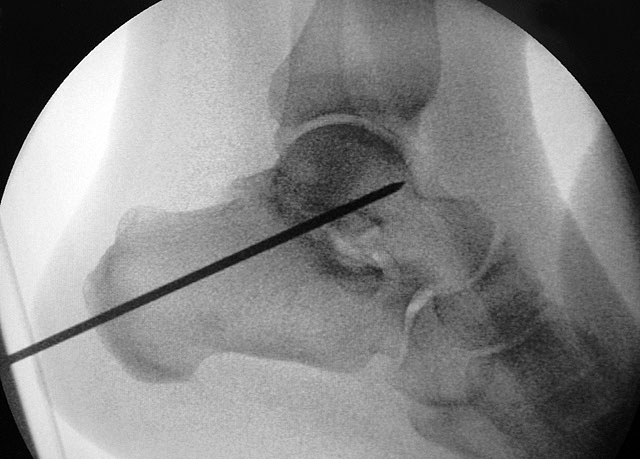

Ziel der Korrektur ist eine Reposition des Kalkaneus in eine physiologische 5° valgus Stellung. Eine Überkorrektur in Varus ist in jedem Fall zu vermeiden. Die Stellung wird anschließend mit K-Drähten fixiert, über die kanülierte Schrauben eingebracht werden können."> 155.</li>

Ziel der Korrektur ist eine Reposition des Kalkaneus in eine physiologische 5° valgus Stellung. Eine Überkorrektur in Varus ist in jedem Fall zu vermeiden. Die Stellung wird anschließend mit K-Drähten fixiert, über die kanülierte Schrauben eingebracht werden können." srcset="/assets/images/1/3-9tsh2b2m85xxjf3.jpg 1x, /assets/images/q/3-q5j2bj6y0h8725z.jpg 1.5x, /assets/images/k/3-h9kd23kj30b48p9.jpg 2x" width="270" height="240" loading="lazy">

Schraubenfehllage: Bei der intra-operative Röntgen-Kontrolle muss der Fuß exakt seitlich und das obere Sprunggelenk ap eingestellt werden, um die korrekte Lage der Schrauben beurteilen zu können.